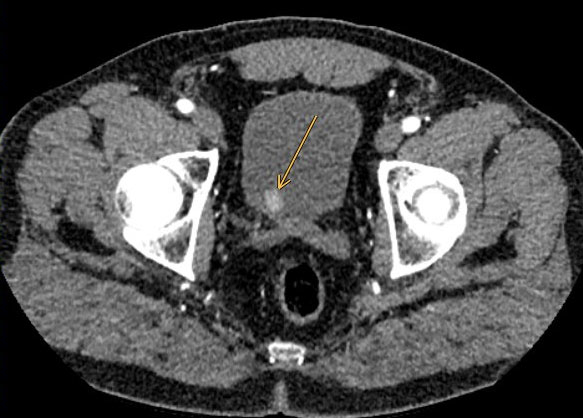

A total of 85/200 patients (42.5%) exhibited incidental findings requiring immediate further medical workup and/or treatment. Of note, most incidental findings here were newly diagnosed cardiovascular conditions, with coronary artery calcification being the most prevalent finding followed by arterial aneurysms and incidentally detected embolism (table 2, figs 1, 2a and 2b ). Pancreatic and liver tumours were less frequent, but significant. Examples of incidentally diagnosed tumours are shown in figures 3 and 4 .

Figure 1 Axial CT scan of the left coronary artery in a 43-year old ED patient showing coronary artery calcification which led to a coronary angiogram.

Most of the findings considered to require immediate treatment were related to CAC. CAC was seen on CT scans in over 37.5% of ED patients. Thus, coronary atherosclerosis was incidentally diagnosed in more than 20% of patients in our study. According to the American College of Radiology, assessing the presence of CAC on CT scans may be valuable to the patient and referring physician, either for reassurance that no CAC is present or to increase patient awareness of coronary heart disease risk, and to stimulate discussion and further workup of cardiac risk factors [17]. Thus, based on these findings, a significant number of previously asymptomatic patients may have had an additional benefit from the CT scan performed for workup of ED.